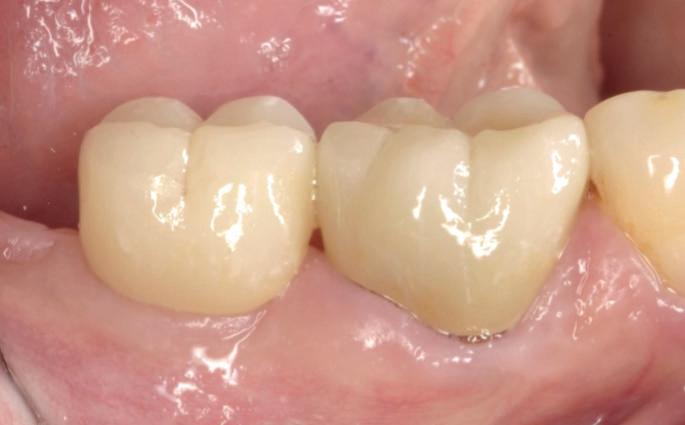

Toen wij in 2009 begonnen met het vormgeven van een molaarkroon op een implantaat als een premolaar met kleine mesiale of distale dummy was dat schoorvoetend en gebaseerd op de wetenschap uit 1 overzichtsartikel. Inmiddels is deze manier van restaureren verder onderzocht en heeft het een solide basis gekregen.

In een eerder artikel in Dentista (2019 issue 5) met de titel ‘Champignon of tulp?’ schreven we dat op basis van wat wij aan complicaties krijgen verwezen, het erop lijkt dat men ervan uitgaat dat overhang bij restauraties op implantaten geen probleem is. Gezien de bekende negatieve effecten van overhangende restauraties op het parodontium bij natuurlijke gebitselementen, is het echter niet verrassend dat implantaatgedragen suprastructuren met een paddenstoelachtige vorm problemen veroorzaken. In feite is het falen bij deze vormgeving al vanaf het ontwerp ingebouwd (afbeelding 1a-d).

In een meer recent artikel in Dentista (2020 issue 4), getiteld ‘De ideale vorm’, werd benadrukt dat de ‘emergence angle’ bij bone-level implantaten een belangrijke factor is in de ontwikkeling van peri-implantaire ontstekingen. Retrospectief onderzoek toont aan dat de prevalentie van peri-implantitis significant hoger is bij een emergence hoek groter dan 30 graden, vergeleken met abutments waarbij deze hoek kleiner is dan 30 graden. Recent werd dit opnieuw onderbouwd in een preklinische studie, waarin restauraties werden geplaatst met een emergence-profiel variërend van 20, 40, 60 of 80 graden (Strauss et al., 2024). Na 24 weken bleek dat grotere restauratieve hoeken leiden tot meer marginaal

botverlies. De auteurs concluderen daarom dat het verstandig is om de hoek zo smal mogelijk te houden, bij voorkeur onder de 40 graden. In de praktijk blijkt echter dat het niet altijd mogelijk is om een zo klein mogelijke restauratiehoek te gebruiken. Bijvoorbeeld wanneer er sprake is van een beperkte intermaxillaire ruimte. Om goed uit te komen met de suprastructuur zou dan een grotere restauratiehoek gebruikt moeten worden.

Bij bone-level implantaten met platform-switching is de diameter van het abutment op implantaat niveau kleiner dan die van het implantaat. Hierdoor is het risico groter dat, om occlusaal voldoende breedte te verkrijgen, er een te grote emergence angle ontstaat, wat resulteert in een te bolle kroon. Daarom is het bij de keuze voor een platform-switch implantaat in de basis essentieel om ofwel een implantaat met een grotere diameter te selecteren, ofwel het implantaat relatief dieper te plaatsen. Dit helpt om een optimale emergence te verkrijgen met een geschikte hoek en bolling vanaf het abutment naar de implantaatkroon.

Voor tandartsen en tandtechnici is het verleidelijk om de suprastructuur te modelleren naar de oorspronkelijke vorm van het verloren gegane element (zie figuur 1). Als de beschikbare botbreedte het toelaat, is het daarom wenselijk om in de molaarstreek

1a-d. Een mooi vormgegeven kroon op element 47, maar deze ligt als een balkon bovenop de gingiva, waardoor het implantaat niet te sonderen is – laat staan dat de patiënt het goed kan reinigen.

een implantaat met een grotere diameter te plaatsen. In veel klinische situaties is dit echter niet mogelijk, waardoor een aangepaste vormgeving overwogen moet worden. Onze boodschap in de vorige twee artikelen was: denk in dergelijke gevallen in termen van een ‘premolaar’. Deze vormgeving sluit beter aan bij de afmetingen van een implantaat en biedt een voorspelbaardere langetermijnprognose.

Met in het achterhoofd dat het premolariseren van suprastructuren een gunstiger emergence profile geeft en een eenvoudiger te reinigen peri-implantaire situatie oplevert, bracht dit ons, naar aanleiding van een artikel van Aglietta et al. (2009), ertoe om in diverse casussen te kiezen voor een molaar die is vormgegeven als een premolaar met een kleine dummy. Maar zoals al gezegd, gebeurde dit schoorvoetend, omdat we ons ervan bewust waren dat kroon- en brugwerk met cantilever extensies op natuurlijke gebitselementen lagere overlevings- en succespercentages vertonen na een periode van 5 en 10 jaar (Pjetursson et al., 2004). De voorspelbaarheid op lange termijn voor implantaten was echter onduidelijk. Daarom was de uitkomst van de systematische review van Aglietta et al. (2009) interessant, omdat deze auteurs de overlevingspercentages van reconstructies op implantaten met cantilevers probeerden vast te stellen na een observatieperiode van mini-

maal 5 jaar. Hun conclusie was dat dit type restauratie kan worden beschouwd als een voorspelbare en betrouwbare vervanging van ontbrekende molaren bij gedeeltelijk edentate patiënten. Er werden geen nadelige effecten op het botniveau waargenomen rondom implantaten in de nabijheid van de cantilever extensies. Het onderzoek van Tuna et al. (2019) laat zien dat onze veronderstelling klopt: een kroon met een kleine dummy zorgt voor betere approximale reiniging, waarbij er dichter bij het implantaat gereinigd kan worden.